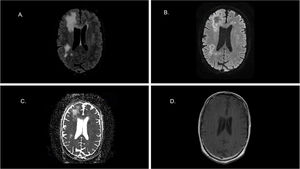

A cerebral CT scan demonstrated multifocal white matter lesions, raising suspicion of PML. Subsequent brain MRI revealed multiple supratentorial myelinoclastic lesions consistent with PML. Cerebrospinal Fluid (CSF) analysis showed no pleocytosis, normal glucose, protein, and lactate levels, a negative bacterial culture, and a JC virus PCR result of 150,236 copies/mL. PCR was performed using the JCV ELITe MGB® and BKV ELITe MGB® kits on the ELITe BeGenius analytical platform from ELITech, with respective limits of quantification in blood and CSF of 306 copies/mL and 239 copies/mL for JCV; 165 copies/mL and 250 copies/mL for BKV (Fig. 1 and 2).

(A) 3D-FLAIR image shows areas of hyperintense signal in the white matter of the right hemisphere involving the U fibers. (B) DWI and respective ADC map (C) show that lesions manifest a hypersignal wavefront spreading without diffusion restriction (lack of hyposignal in ADC map). This finding indicates an activee myelinoclastic process at the wavefront. (D) The axial T1 image after contrast medium administration shows no enhancement of the lesions.